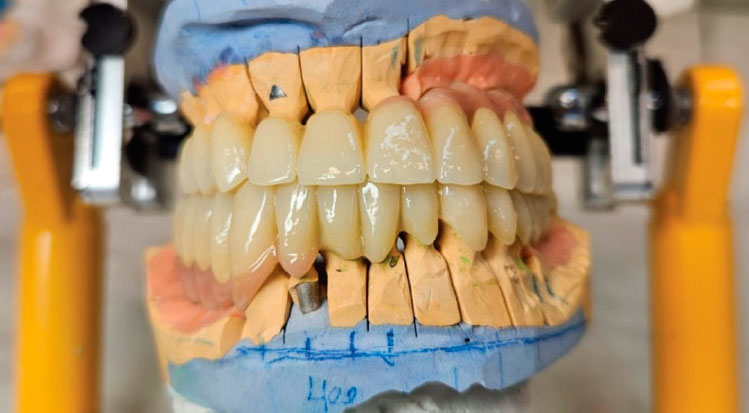

Проведено восковое моделирование в соотношении зубных рядов, полученном после лечения на каппе (рис. 9).

Рис. 9. Восковое моделирование в полученном соотношении зубных рядов

Fig. 9. Wax model of the resulting occlusion